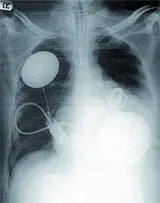

Искусственный хрусталик глаза или искусственный сердечный клапан давно вошли в клиническую рутину. Полностью искусственный глаз — пока мечта, но уже приобретающая зримые очертания.

А вот полностью искусственное сердце — очень условная и очень штучная, но уже реальность.

И все-таки, несмотря на радужные перспективы генеральной линии, они еще очень долго останутся лишь перспективами. Тем более сильное впечатление производят успехи «обычных» технологий изготовления органов из подручных, так сказать, материалов. Несомненный хит прошедшего года — искусственное сердце Abiocor. Собственно, впервые этот девайс был имплантирован человеку еще 21 августа 2001 года (а началом программы по его созданию была инициатива тогдашнего президента США Линдона Джонсона, объявленная в мае 1964 года [В годы правления Джонсона его имя связывали в основном с политикой эскалации войны во Вьетнаме, начавшейся с инцидента в Тонкинском заливе 2 августа того же 1964 года и унесшей сотни тысяч жизней. А в наши дни Джонсон — тот, в честь кого назван космический центр НАСА, да еще и инициатор создания искусственного сердца. Иронично получилось]; в Японии аналогичная работа велась с 1960 года). Abiocor пока что помог лишь немного продлить жизнь четырнадцати безнадежным пациентам (лучшие результаты были у двоих — они прожили после операции десять и семнадцать месяцев, и лишь один был выписан из больницы домой). Устройство работает от батарейки, которую надо подзаряжать (индукционно, через кожу) каждый час. Однако очевидно, что это полностью имплантируемое искусственное сердце — лишь первый шаг. Фирма ABIOMED сейчас тестирует искусственное сердце второго поколения, которое, как предполагается, должно работать в течение пяти лет (нынешняя модель рассчитана на восемнадцать месяцев). Но что же произошло в сентябре прошлого года, спустя пять лет после первой операции? Почему этот момент был сочтен специалистами ключевым и широко освещался в СМИ всего мира?